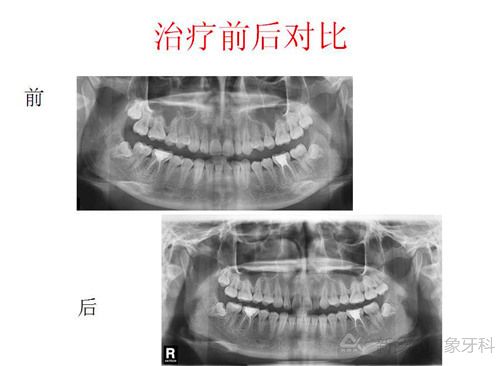

治疗计划:全口直丝固定矫治术,牙齿排齐与整平,解决覆合覆盖关系,调整磨牙咬合关系,精细调整,保持,择期拔除18、28、38、48

结束时间:2015年1月9日

图片为治疗过程及结果。